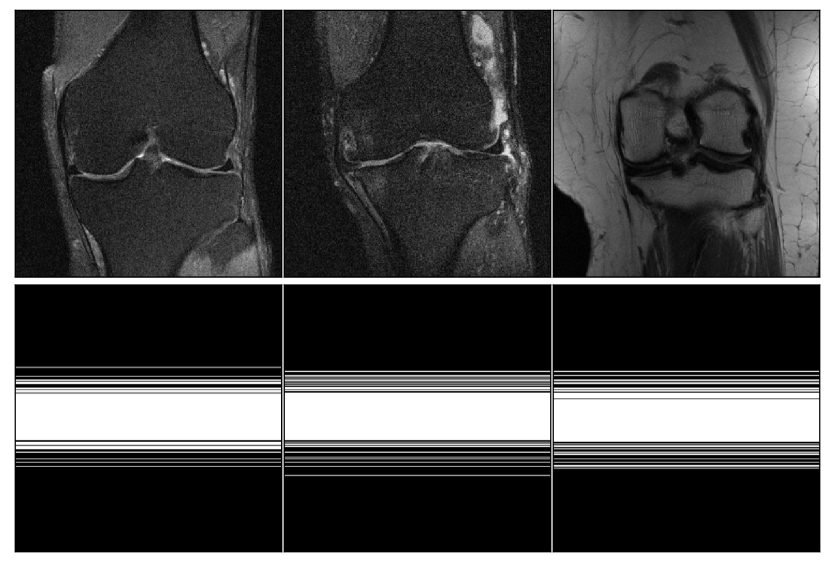

One should note that the adaptive MNet mask shown in Figure 5 is for the ground truth object in Figure 4, while the underlying probabilistic parametrization of LOUPE mask in Figure 5 is fixed after the training process completes with respect to the training dataset. The random mask is re-generated for each different input during the training and testing process, so the random mask used in the sampling process can differ from one object to another. The equi-distance mask is fixed with respect to the entire training and testing dataset given the pre-assigned amount of low frequencies observed and the amount of sampling budget for remaining high frequencies.

Refer to caption

Figure 5: Comparison of different masks with respect to the object in Figure 4 with 8×8\times acceleration.

Figure 8: Comparison of different masks with respect to the object in Figure 7 at 4×4\times acceleration.